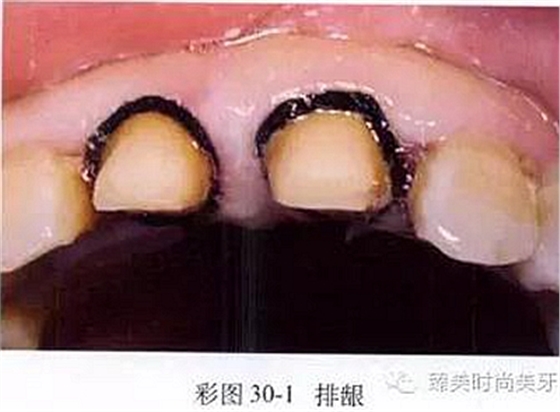

(3)組織處理:制取印模前,為使齦溝敞開(kāi),肩臺(tái)預(yù)備或形態(tài)復(fù)制更準(zhǔn)確、清晰,應(yīng)進(jìn)行排齦操作(彩圖30-1),使齦溝更敞開(kāi)。同時(shí),排齦也可起到降低齦溝液分泌和部分止血的作用。

操作時(shí)以氣槍噴霧沖洗齦溝內(nèi)的唾液或血液,以棉卷隔濕,剪取一段專(zhuān)用齦收縮線(xiàn)或浸有牙齦收縮劑的無(wú)蠟牙線(xiàn)(齦收縮線(xiàn)的直徑以不超過(guò)齦緣線(xiàn)為準(zhǔn)),以牙科鑷環(huán)繞牙頸部,并以壓齦器壓人齦溝內(nèi)。收縮線(xiàn)填人齦溝時(shí)動(dòng)作應(yīng)輕柔,禁止用力超過(guò)5g,以防止破壞結(jié)合上皮的完整性。填壓時(shí)棉線(xiàn)按照從近中鄰面中央處延伸,環(huán)繞頰面并至遠(yuǎn)中鄰面區(qū)的方向進(jìn)行。填壓后棉線(xiàn)需在固定位置保持2~3分鐘,棉線(xiàn)還需保持濕潤(rùn),以避免撕裂脆弱的結(jié)合上皮引發(fā)出血。